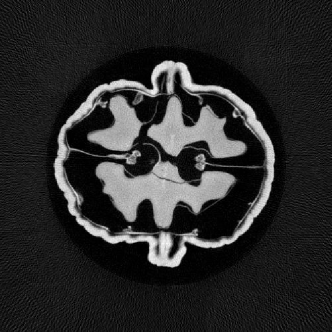

In Fig. 4, a comparison of the central slice of volumes reconstructed with different redundancy weights is presented. The results show that the neural network, after training, can achieve reconstruction results similar to those obtained through analytical methods.

Refer to caption

(a)

(b)

(c)

Figure 4: Reconstructed results of the network. (a) Reconstruction using learned redundancy weight. (b) Reconstruction using analytic redundancy weight. (c) FDK reconstruction result.